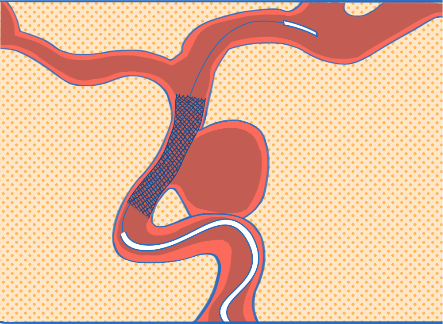

颅内动脉瘤发生、进展和破裂的一个主要因素被认为是血流动力学障碍,故动脉瘤的治疗目标是重建血管壁和纠正血流动力学紊乱。近年来新发展的血流导向装置具有血流动力学和生物学的效应,可以通过改变血流方向促进动脉瘤内血流淤滞并形成血栓;同时促进支架内的内皮细胞和新生内膜组织增生,进而依靠瘤颈的内膜化达到修复载瘤动脉的作用。血流导向装置的出现使巨大的囊性或梭形动脉瘤的治疗模式由瘤体栓塞转为载瘤血管的重建。这是一项革命性的飞跃,开创了颅内动脉瘤介入治疗的新纪元,使得介入治疗更加方便快捷。

血流导向密网支架重建